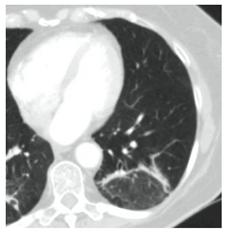

2. Наличие клинических проявлений, указанных в п. 1, в сочетании с характерными изменениями в легких по данным компьютерной томографии (КТ) (см. Приложение 1 настоящих рекомендаций) вне зависимости от результатов однократного лабораторного исследования на наличие РНК SARS-CoV-2 и эпидемиологического анамнеза.

- Изменения при КТ (рентгенографии), типичные для вирусного поражения (объем поражения минимальный или средний; КТ 1-2)

- Изменения в легких при КТ (рентгенографии), типичные для вирусного поражения (объем поражения значительный или субтотальный; КТ 3-4)

- Изменения в легких при КТ (рентгенографии), типичные для вирусного поражения критической степени (объем поражения значительный или субтотальный; КТ 4) или картина ОРДС.

КТ имеет высокую чувствительность в выявлении изменений в легких, характерных для COVID-19. Применение КТ целесообразно для первичной оценки состояния ОГК у пациентов с тяжелыми прогрессирующими формами заболевания, а также для дифференциальной диагностики выявленных изменений и оценки динамики процесса. КТ позволяет выявить характерные изменения в легких у пациентов с COVID-19 еще до появления положительных лабораторных тестов на инфекцию с помощью МАНК. В то же время, КТ выявляет изменения легких у значительного числа пациентов с бессимптомной и легкой формами заболевания, которым не требуется госпитализация. Результаты КТ в этих случаях не влияют на тактику лечения и прогноз заболевания при наличии лабораторного подтверждения COVID-19. Поэтому массовое применение КТ для скрининга асимптомных и легких форм болезни не рекомендуется.